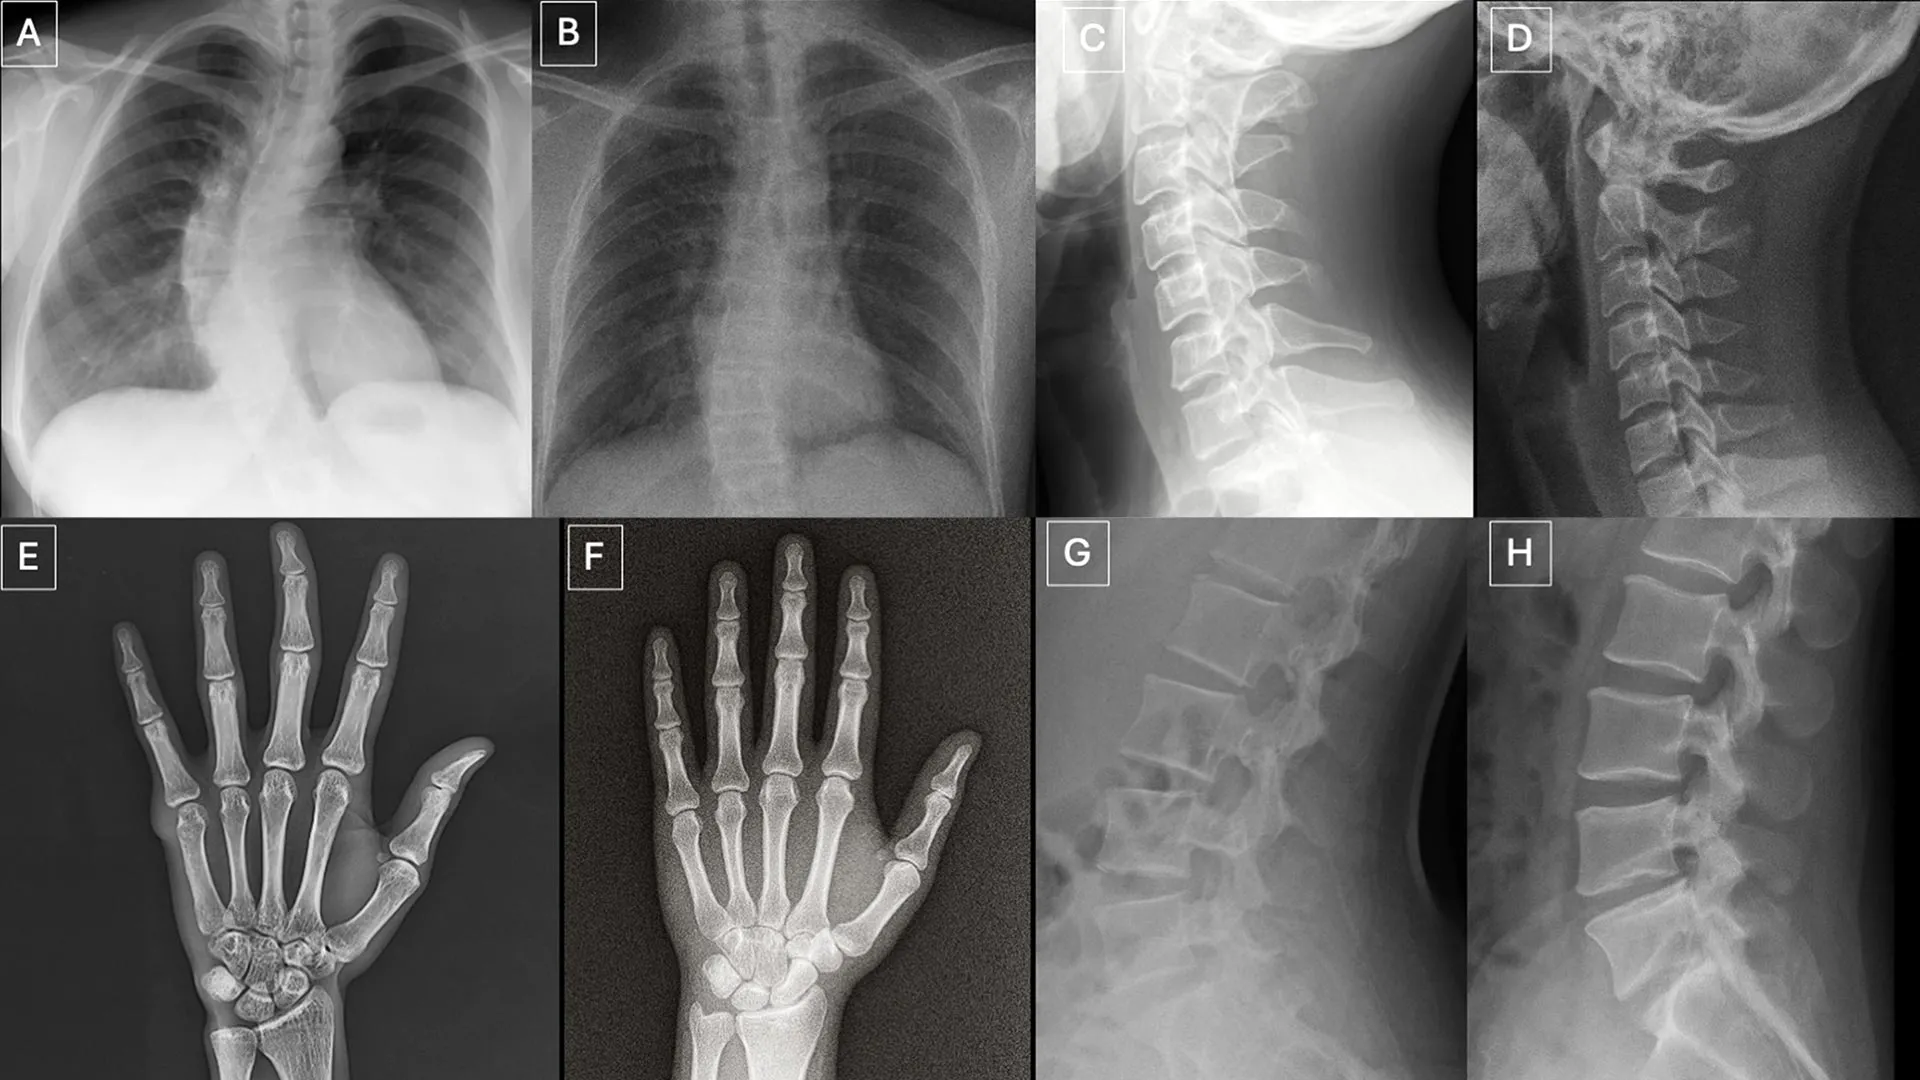

Participants reviewed two separate sets of images with no overlap. One set had a mix of real images and ChatGPT-generated X-ray images from different parts of the body. The second set focused on chest X-rays, half real and half created using RoentGen, an open-source generative AI diffusion model developed by researchers at Stanford Medicine.

Researchers have identified several patterns that can appear in synthetic images.

“Deepfake medical images often look too perfect,” says Dr. Torjman. “The bones are overly smooth, the spine is unnaturally straight, the lungs are overly symmetrical, the pattern of blood vessels is overly uniform, and fractures appear unusually clean and consistent, but are often confined to one side of the bone.”